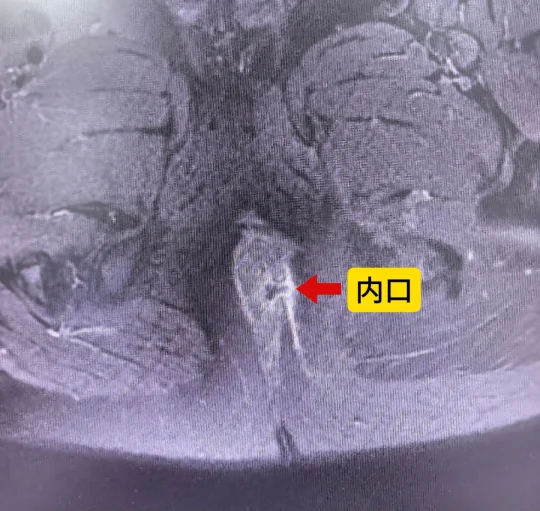

图中术前看起来就像个低位肛瘘,但做做完磁共振是个高位肛瘘,所以有时候肛瘘比你想象的要复杂!临床经验是一方面,但检查可以减少漏诊率;肛周磁共振对于肛瘘的走行和内口的位置有很好的显示作用,可以指导手术,避免遗漏细小的分支瘘管,防止复发!